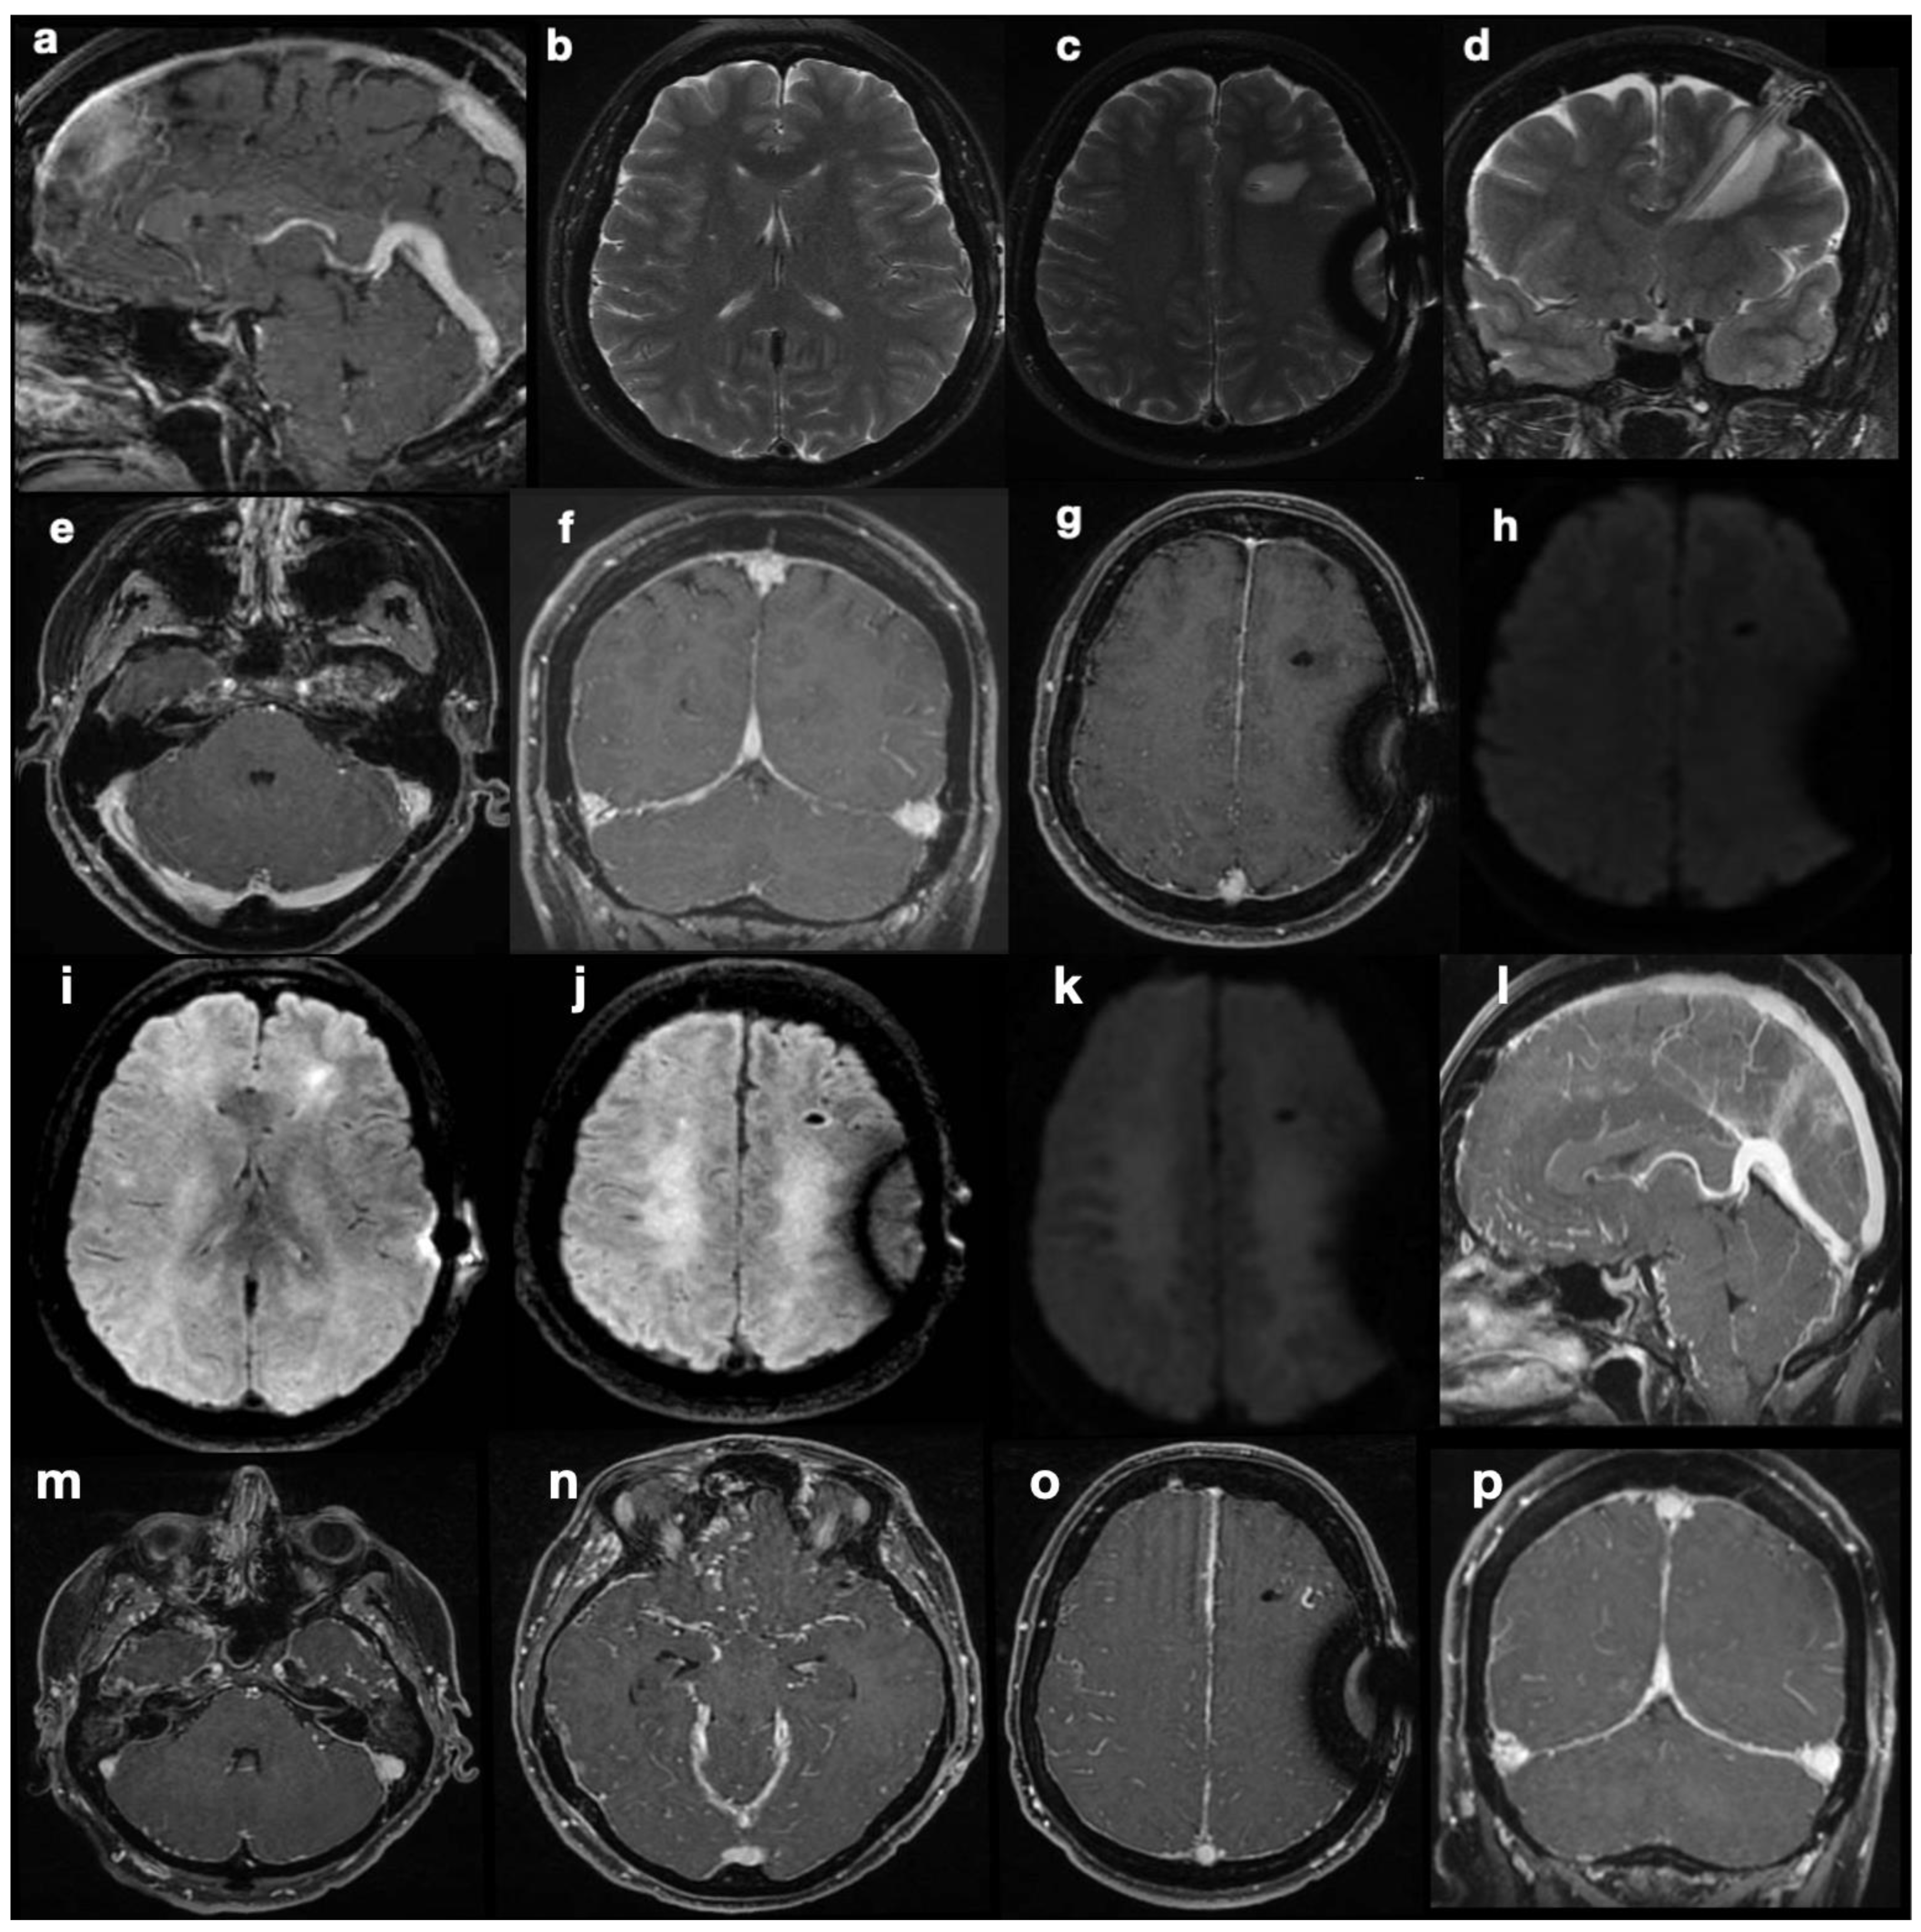

She was diagnosed with idiopathic intracranial hypertension (IIH) based on a highly suggestive clinical presentation (chronic and drug-resistant cephalgia and progressive visual loss with no alternative explanation). MRI, performed upon the patient’s admission (Figure 1), showed asymmetry of the transverse sinuses, suggesting incomplete stenosis (a), mild turgidity of the optic nerve sheath (b), and normal ventricles (c). Together, these findings strengthened the suspicion of IIH [1,2]; therefore, the patient was referred for neurosurgical treatment. Placement of a ventriculoperitoneal shunt (VPS) (Hakim Codman programmable valve, initial valve-opening pressure of 140 cmH2O) revealed intracranial hypertension and led to symptom relief. Normal CSF composition and the absence of localizing signs or intracranial masses confirmed the diagnosis of IIH according to modified Dandy’s criteria [3].

Figure 1. Preoperative MRI. Images showing the findings of the asymmetry of transverse sinuses (a), optic nerve sheath enlargement (b), and normal ventricles (c), compatible with intra-cranial hypertension.